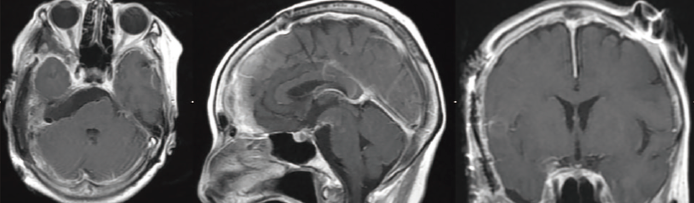

頭蓋底手術 脳腫瘍の症例

手術前

手術後

鍵穴手術 髄膜腫の症例

脳ドックで髄膜腫という脳腫瘍が見つかった患者さんの症例です。手術前のシミュレーション結果では、脳腫瘍にも鍵穴手術が可能と判断され、手術を実施。腫瘍は全摘出され、7年以上再発はありません。

(68歳・女性/ 青い矢印の部分が髄膜腫)